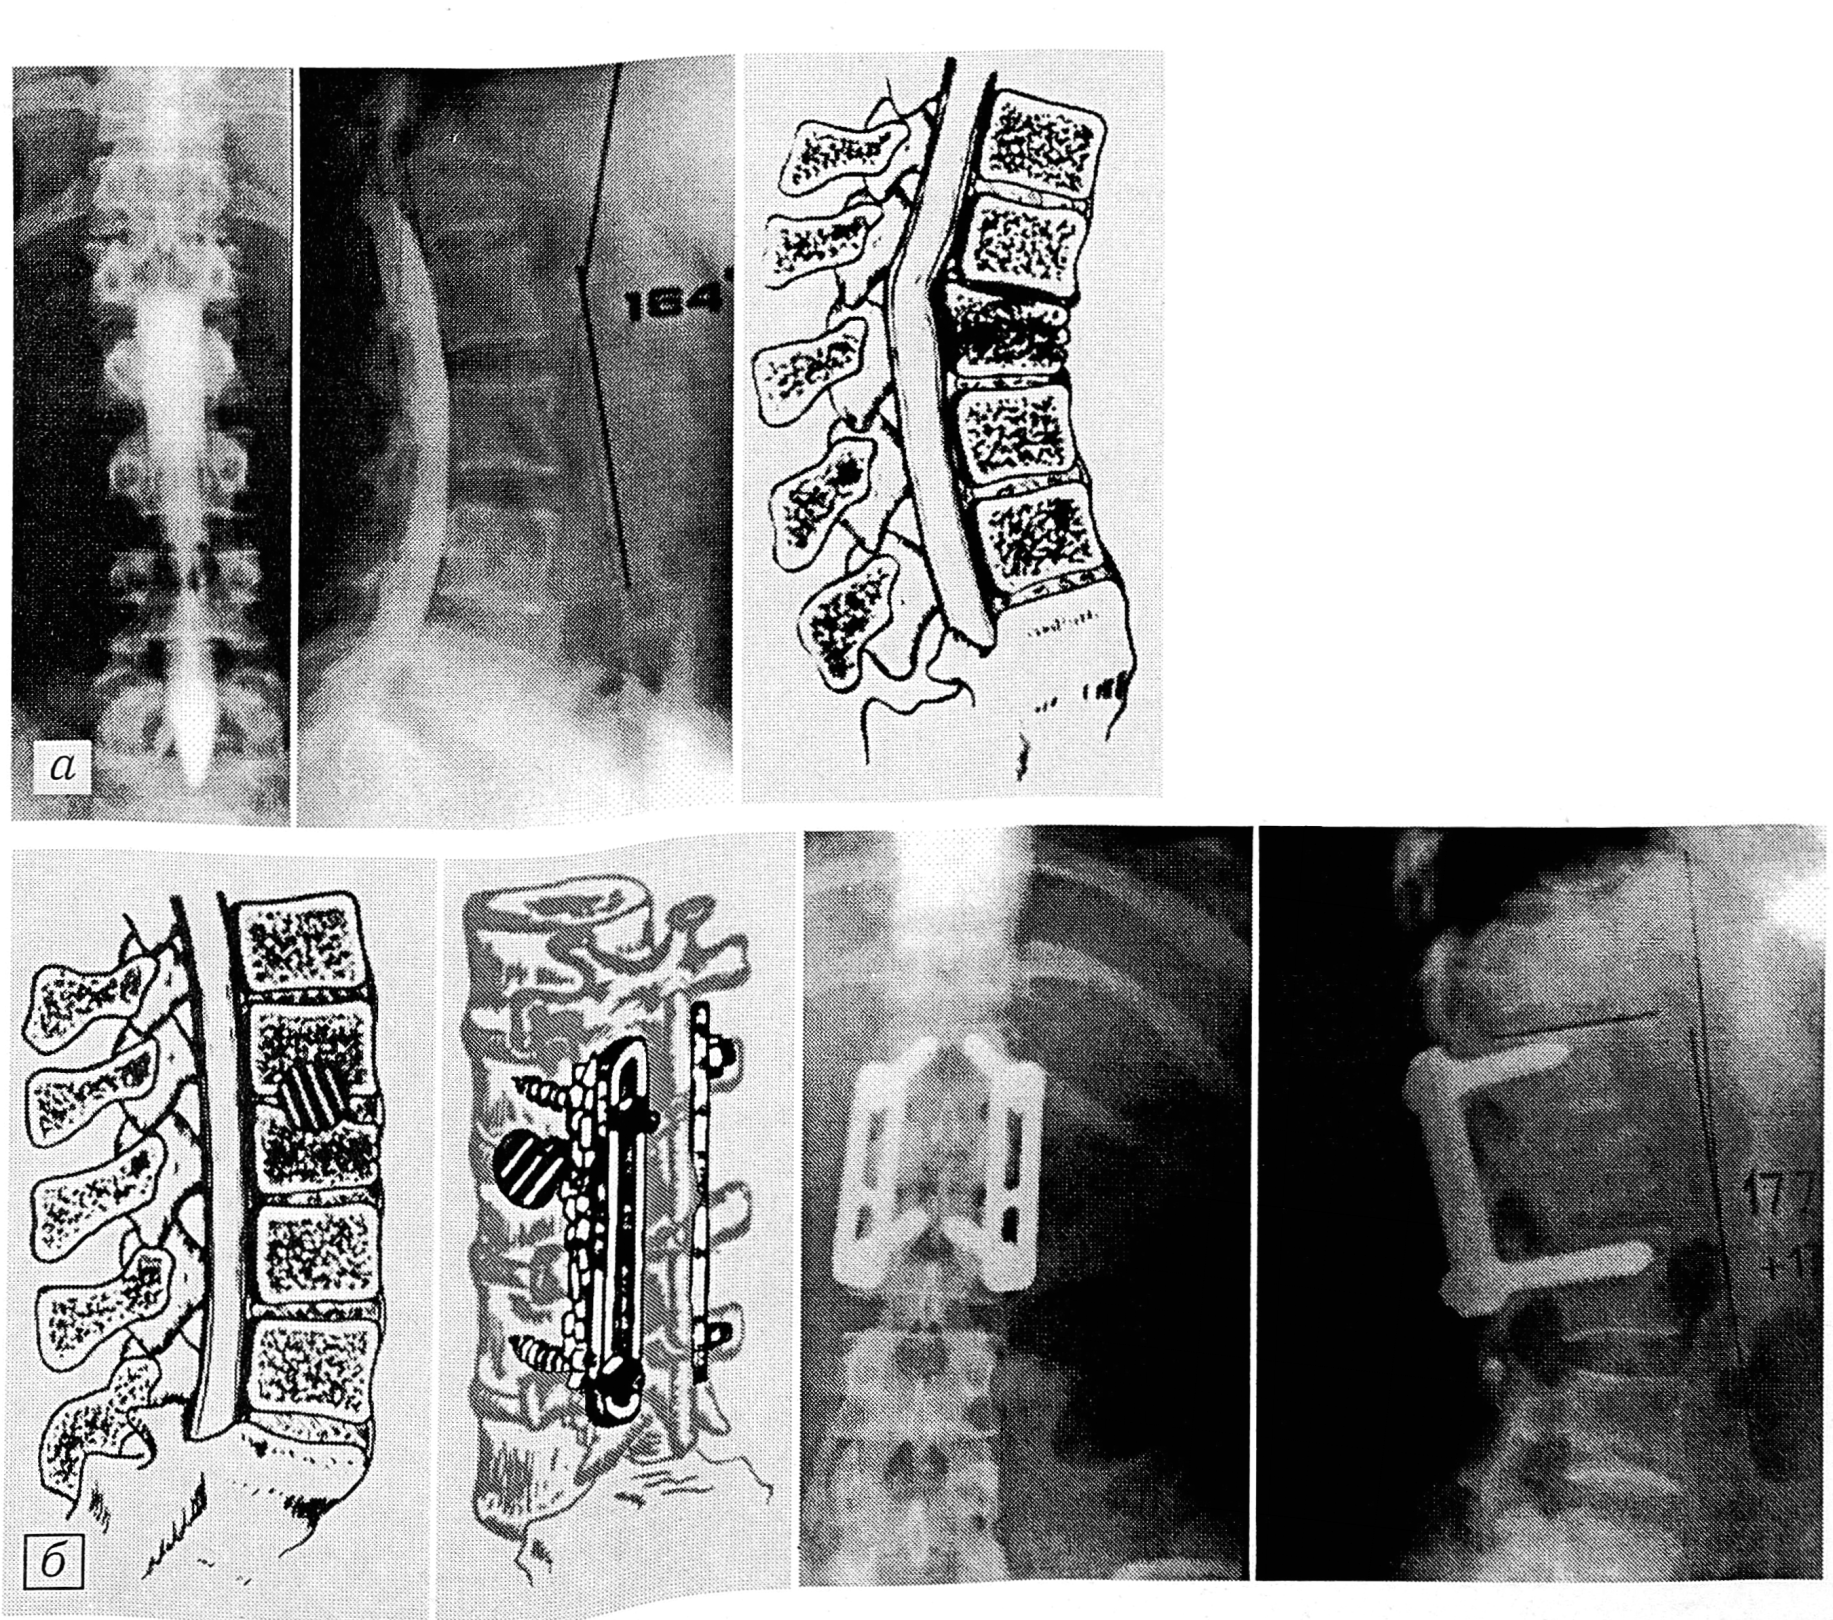

Если имелся перелом двух позвонков, а следовательно, требовалась фиксация позвоночника на большем протяжении, и дополнительными методами исследования выявлялось значительное (более чем на 1/3) сдавление дурального мешка, для фиксации позвоночника использовали стержень Luque, при этом обязательно производили ламинэктомию на уровне перелома с резекцией клина Урбана (с целью декомпрессии спинного мозга). Металлофиксацию позвоночника также сочетали с задним спондилодезом (см. рис. 3).

Рис. 3. Больной Ю.

Травма получена в результате падения в шахту лифта (с высоты 6-го этажа). Перелом Т12—L1 позвонков, сопровождающийся сдавлением дурального мешка до 1/3 диаметра (а). Клинико-неврологически: выраженный болевой синдром, симптомы натяжения, гиперрефлексия, затруднение мочеиспускания. Операция (б): расширенная ламинэктомия Т12, резекция клина Урбана, фиксация позвоночника системой Luque, задний спондилодез. Контрольное обследование через 4 года (в).